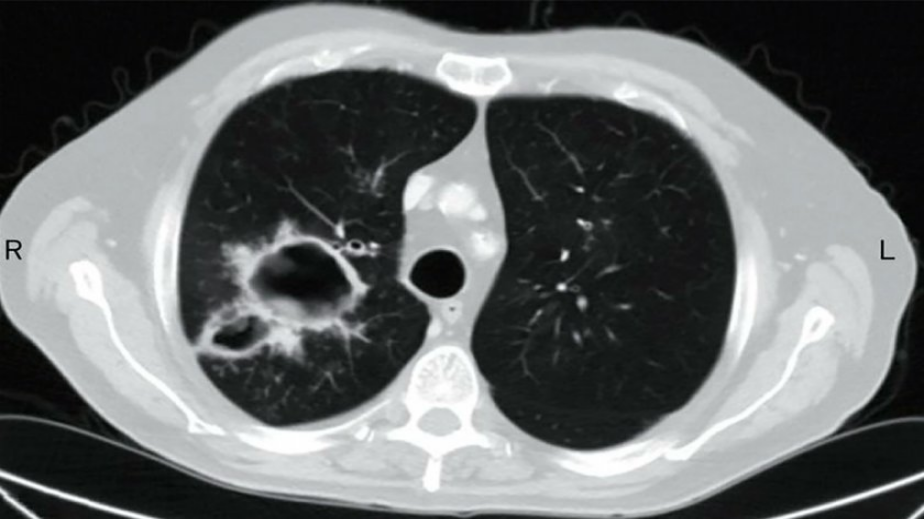

Може да се случи и на хора без рисков фактор за белодробна инфекция с аспергилус? Рентгенографските находки може да изглеждат като белодробни кухини със смущаващи размери – до 12 и повече сантиметра. Гъбичните топкоподобни лезии отнемат дихателен обем и предизвикват тежък задух.

Проф. Даниела Петрова съобщи за пациенти на Александровска болница с аспергиломи и бронхопулмонална аспергилоза, която в голяма степен прилича на астма. А аспергиломът е нещо като топка от гъбички, която се развива в предварително оформени дебелостенни кухини.

Една от находките: кухината с малкото “топче” вляво. Един от случаите, наблюдавани в Отделението по белодробни болести, което проф. Петрова ръководи, е свързан с вида аспергилус негра. Популярен е като черна гъба. При повечето пациенти усложнението е предизвикано от аспергилус фумигатос.